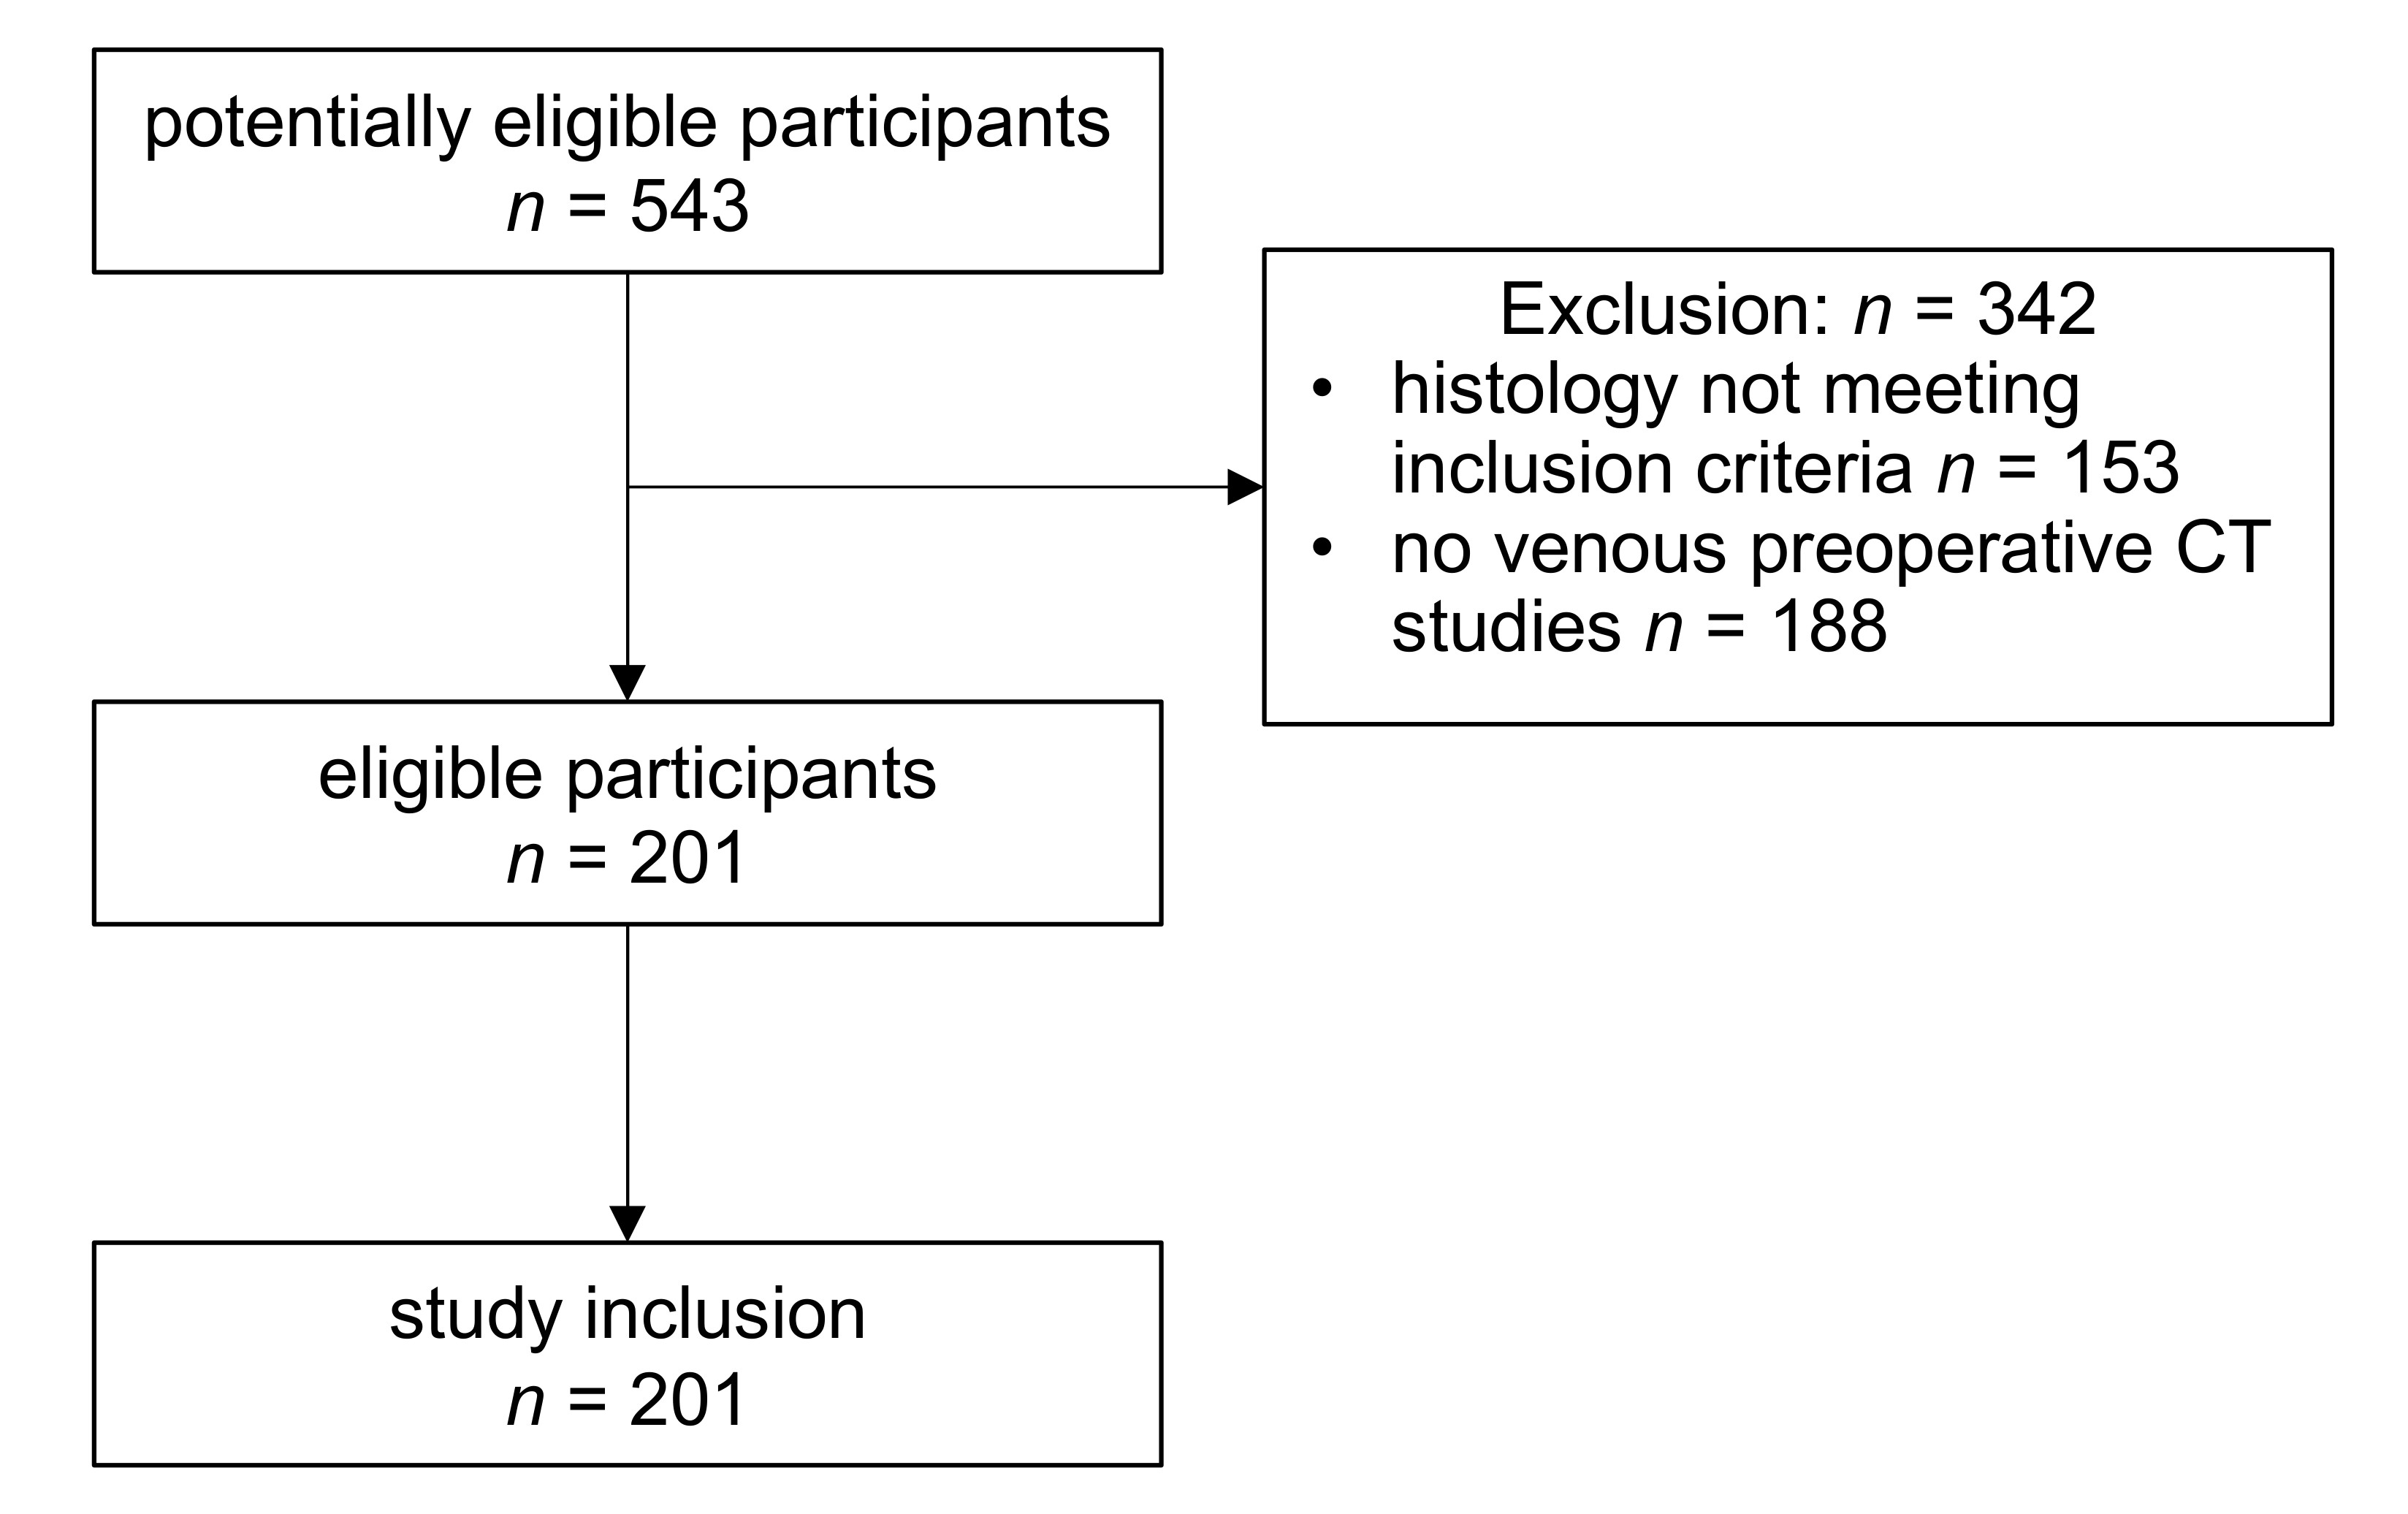

4.1. Study Cohort Selection